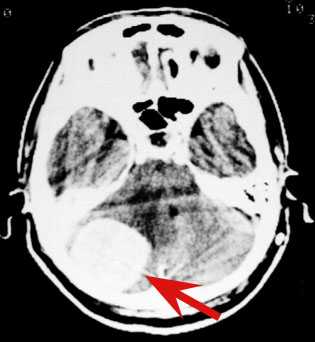

もうかれこれ相当昔になりますが、ある大病院に私が勤務していたころ、消化器内科を「吐き気」を主訴に来院された60歳代の女性が受診し、一生懸命、胃や腸を調べましたが全く異常ありませんでした。ある日、その患者さんが「時々、朝頭痛に悩まされるんです。」と言われましたので、やっと、脳のCT検査が行われたのです。すると、大きな髄膜腫と言われる良性脳腫瘍が発見されたのです。吐き気の原因は頭にありました。脳外科の私に紹介され、私の執刀でこの腫瘍は全摘出され、この患者さんの吐き気と頭痛は見事に消失いたしました。

以下にその画像をお示しいたします。

<赤い矢印が造影された腫瘍です>